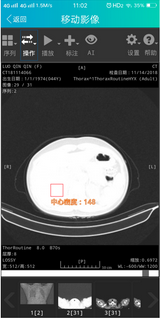

据了解,紛享云影像是以医疗影像智能处理技术为手段,以紛享医疗平台数年积累的海量医疗数据为依托打造的专业医学影像智能处理平台;而移动影像则是在此基础上进行的移动端应用延伸。这两款产品从实用场景层面弥补了诸多现有缺失,可以预见,在未来一段时间,医疗影像AI的应用将迎来大面积的铺开。